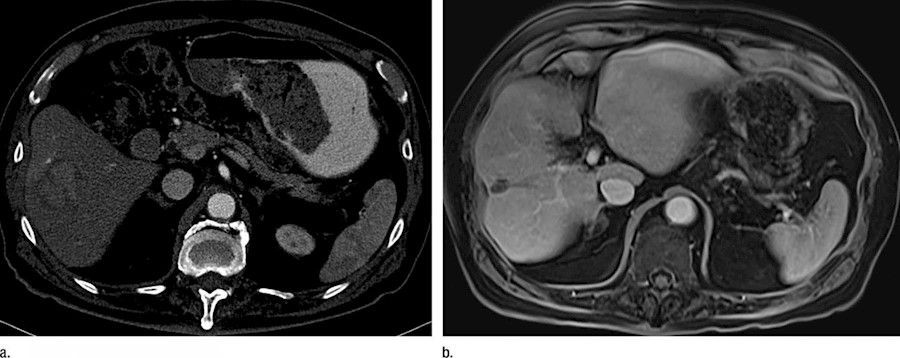

La mayoría de las personas con cáncer de hígado desarrollan primero daño hepático, que a menudo progresa a cirrosis hepática. Una vez diagnosticada, la afección se trata fácilmente mediante un proceso similar a la donación de sangre varias veces al año para reducir los niveles de hierro.